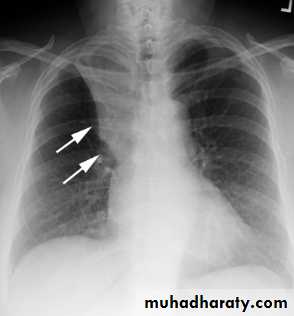

CT lung cavityPulmonary collapse(atelectasis): loss of volume of a lobe or lung, common causes: bronchial obst., pneumothorax or pl. effusion, linear(discoid) atelectasis.

commoner causes of lobar collapse: 1- bronchial wall lesions: us. Primary CA, occasionally others as carcinoid.

2- Intraluminal occlusion: us. FB. Or retained mucus plugs, part. Postop., asthmatic or unconscious pat., patient with artificial vent.

3- invasion or compression by adjacent malig. Tumors, rarely enlarged LNs.

When lobe collapse, the unabsorbed lobe(s) on the side of collapse undergo compensatory expansion, the displaced fissure seen as well defined boundary to airless lobe, the med. And diaph. May move towards collapsed lobe.

RUL collapse +Golden S sign